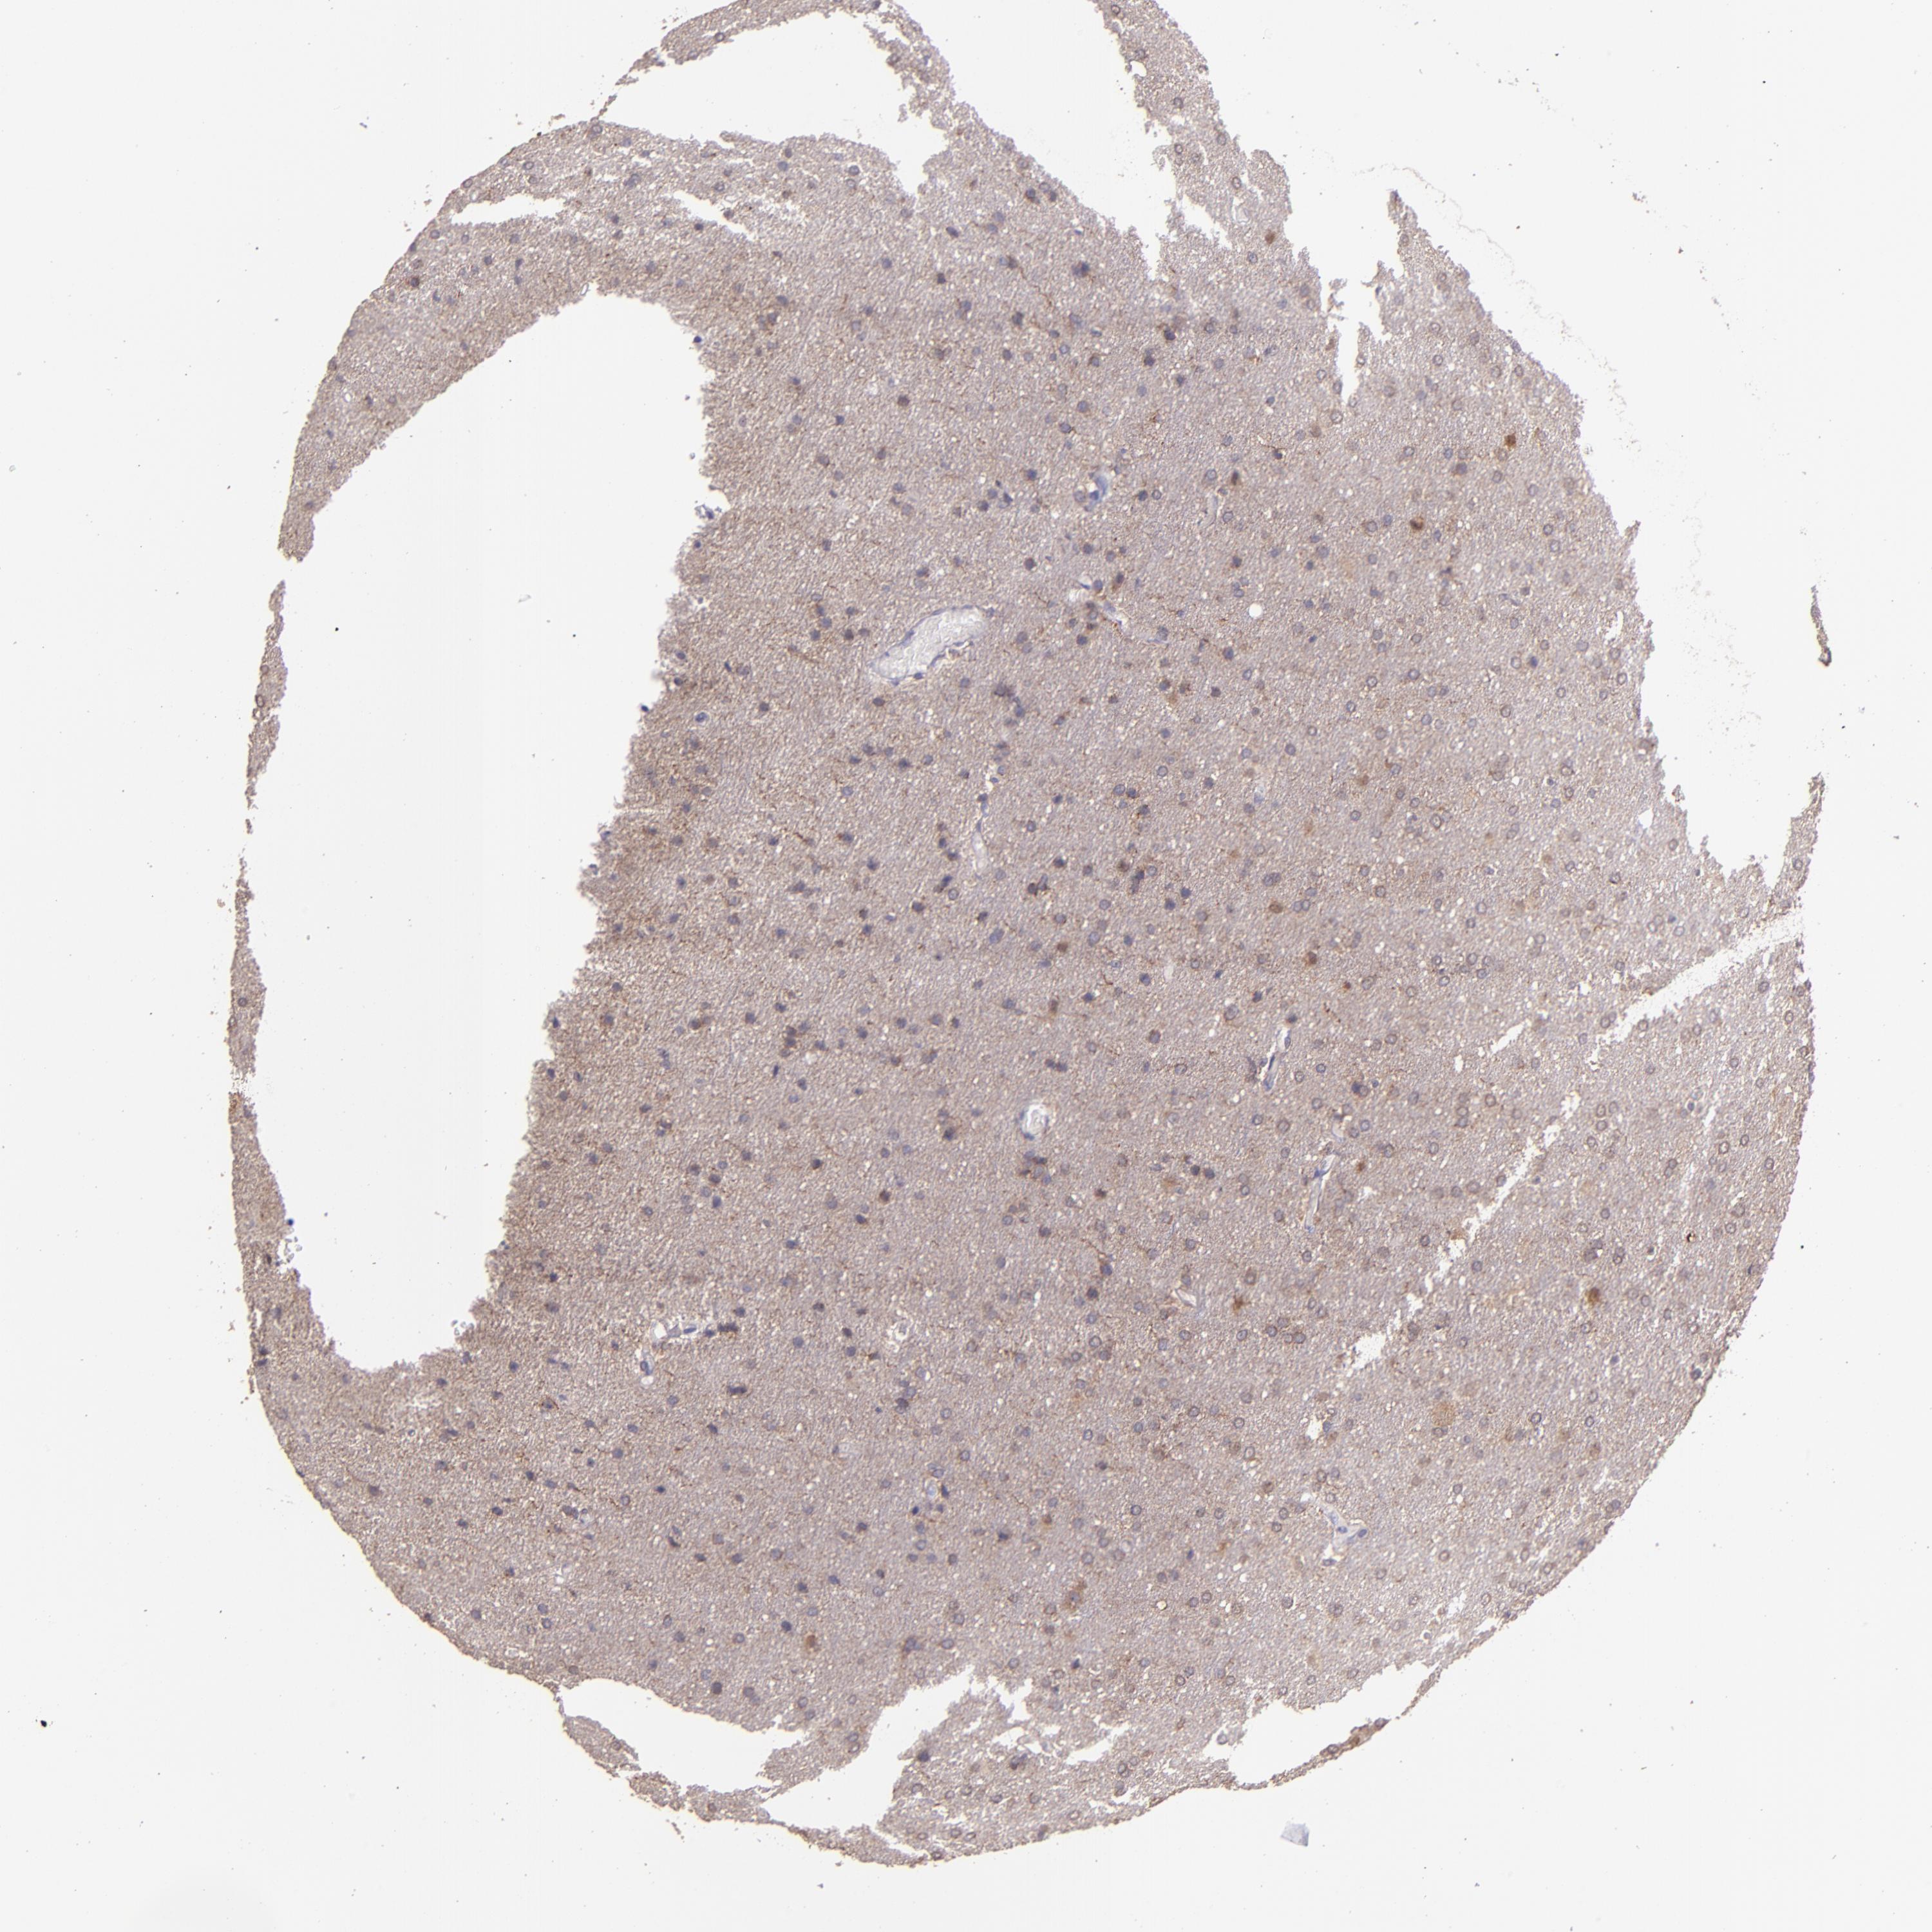

GLIOMA - Protein expressioni

A mouse-over function shows sample information and annotation data. Click on an image to view it in a full screen mode. Samples can be filtered based on level of antibody staining by selecting one or several of the following categories: high, medium, low and not detected. The assay and annotation is described here.

Note that samples used for immunohistochemistry by the Human Protein Atlas do not correspond to samples in the TCGA dataset.

Antibody stainingi

Antibody staining in the annotated cell types in the current human tissue is reported as not detected, low, medium, or high, based on conventional immunohistochemistry profiling in selected tissues. This score is based on the combination of the staining intensity and fraction of stained cells.

Each image is clickable and will lead to virtual microscopy that enables deeper exploration of all samples and also displays staining intensity scores, fraction scores and subcellular localization as well as patient and tissue information for each sample.

Antibody HPA001667

Antibody CAB016724

Staining

High

Medium

Low

Not detected

Intensity

Strong

Moderate

Weak

Negative

Quantity

>75%

75%-25%

<25%

None

Location

Nuclear

Cytoplasmic/membranous

Cytoplasmic/membranous,nuclear

Glioma, malignant, High grade

Glioma, malignant, Low grade

Glioma, malignant, NOS